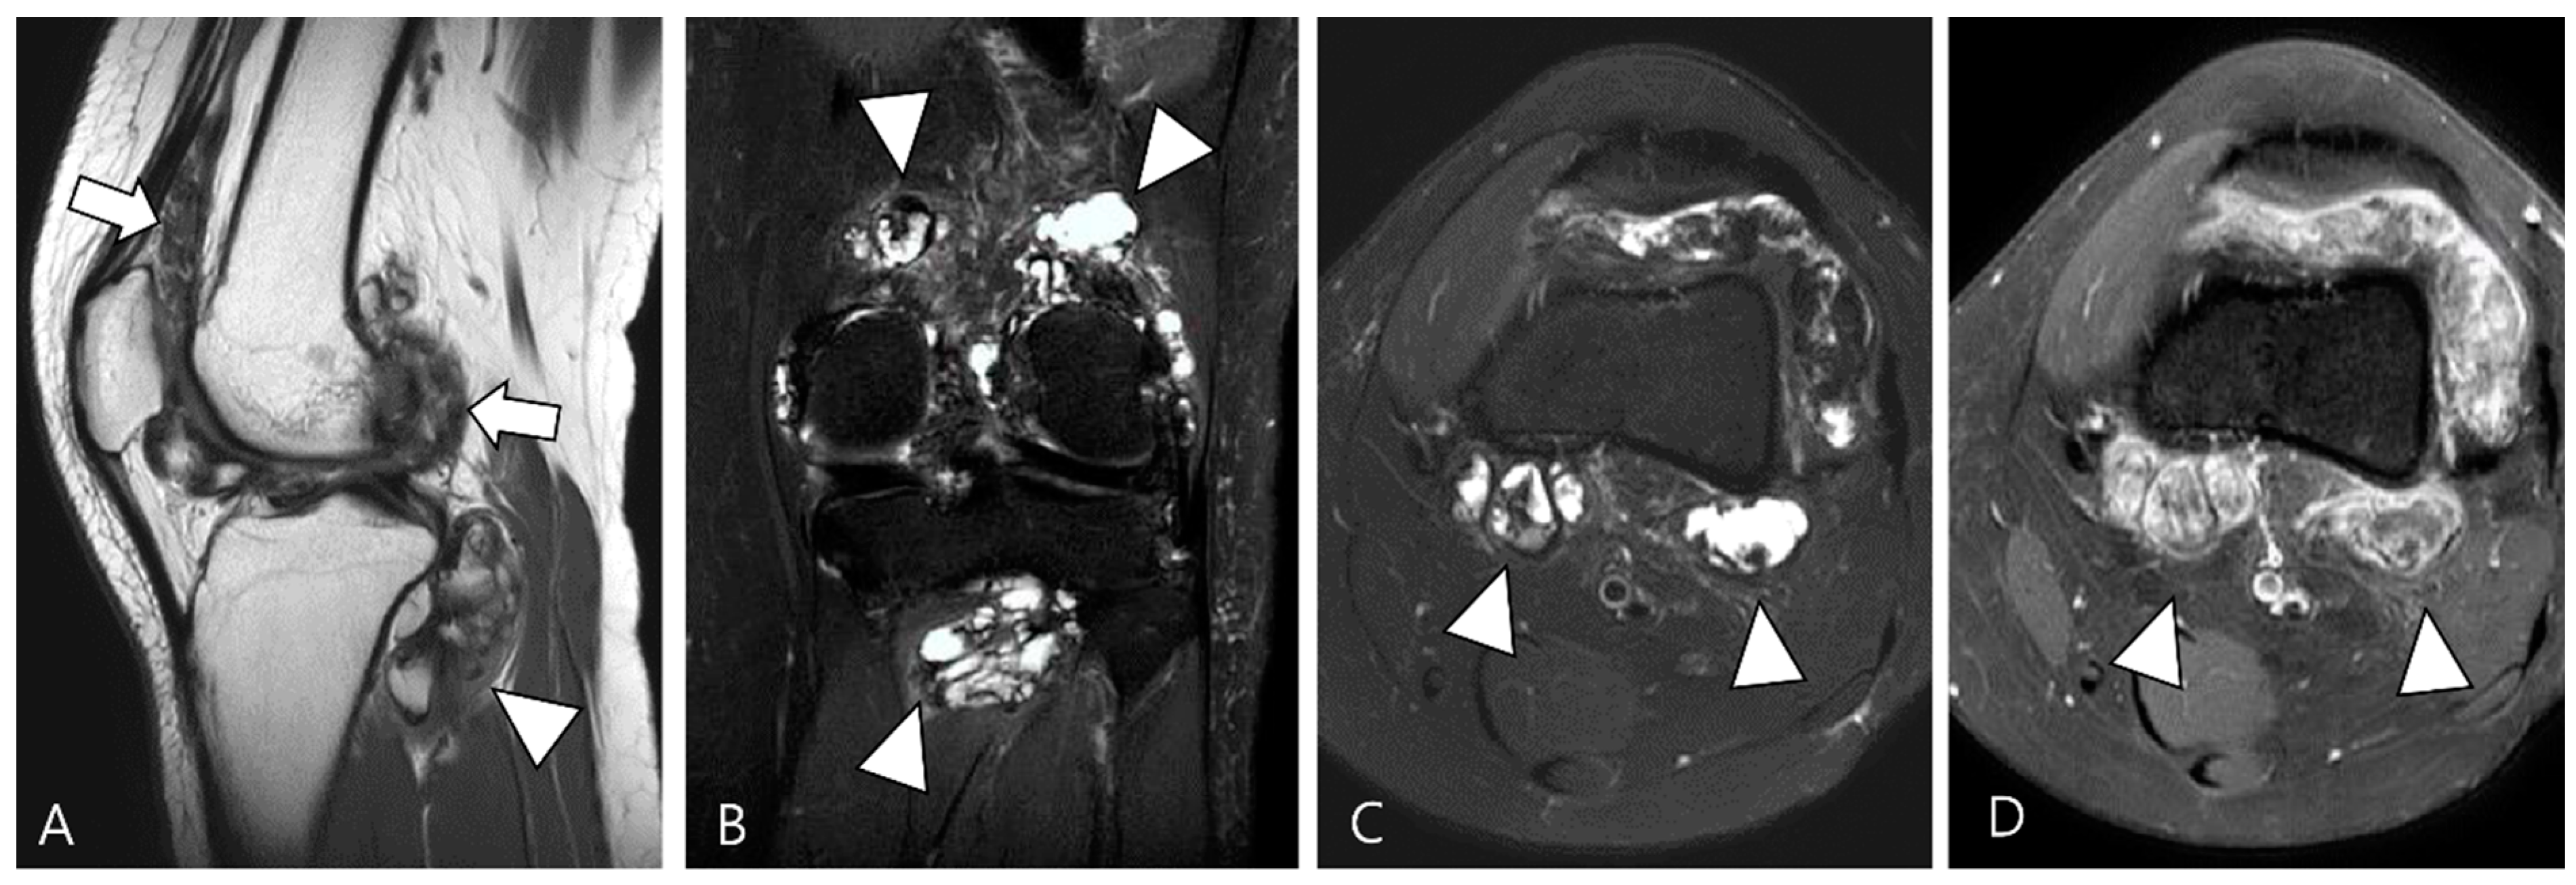

The extra-articular growth of D-TSGCT primarily arises as a result of extra-articular extension of intra-articular D-TSGCT through transcapsular fenestrations (Figure 1 and Figure 3) [31]. However, due to its infiltrative growth pattern, determining the origin is often challenging [32]. Instances of extra-articular D-TSGCT without intra-articular communication are exceedingly rare, and such cases involve the bursa around the knee, such as popliteal bursa (Figure 4) [20,32,33,34,35]. In cases where TSGCTs occur in the digits, they are typically located in extra-articular portion, and it is crucial to differentiate between two subtypes [36]. Jeong et al. [36] conducted a comparison of the MRI morphologic features of TSGCTs in the digits between the diffuse type and localized type. Their findings revealed that D-TSGCTs in digits manifest as multinodular and infiltrative masses without a peripheral capsule. Kim et al. [28] also found that the most sensitive MRI parameter with the highest odds ratio for extra-articular D-TSGCT, which was the lack of peripheral hypointensity (lack of capsule) (Figure 5).

Figure 4.

A 40-year-old female with D-TSGCT in the tibia. (A) Coronal GRE sequence shows a lobulated heterogenous SI mass in the juxtacortical area of the proximal metaphysis of the tibia with blooming artifact (arrow). Note that there is no remarkable intra-articular communication of the knee joint. (B) Axial fat-suppressed T2WI, (C) T1WI, and (D) fat-suppressed enhanced T1WI show the mass arising from the Pes anserine bursa with focal bony erosion of the adjacent tibia (arrowheads) and infiltration to the adjacent muscle and subcutaneous fat layer (asterisks).

Figure 5.

Nodularity, margin, and peripheral hypointensity between two subtypes. (A) Pathology-proven L-TSGCT of the foot shows that the mass is shown as a single mass with a circumscribed margin (arrows) on axial T2WI. The mass shows the avid peripheral hypointensity (see in box) and encasement of the extensor tendon (arrowhead). (B) Pathology-proven D-TSGCT of the foot shows that the masses contain multiple distinct nodules with an infiltrative margin from the surrounding tissues (arrows) on axial T2WI. The masses show the absent peripheral hypointensity (see box) and encasement of the flexor tendon (arrowhead). Box; b = bone, yellow line = tendon.